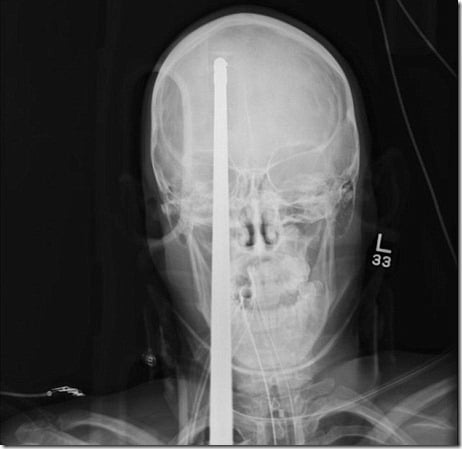

Um garoto de 16 anos Yasser Lopez de alguma forma conseguiu sobreviver a uma lança de 3 metros que entrou em sua cabeça.

O acidente aconteceu quando um arpão foi disparado por engano ao ser carregado, a lança maciça entrou através de seu cérebro com a extremidade saliente chegando a traseira de seu crânio.

Milagrosamente, Lopez não foi morto -. a lança não atingiu os grandes vasos sanguíneos em seu cérebro "É um milagre a lança perdeu todos os principais vasos sanguíneos do cérebro", disse o neurocirurgião Ross Bullock.

"A coisa mais importante é resistir à tentação de puxar essa coisa." Lopez vai passar várias semanas no hospital, mas deve fazer uma recuperação completa.